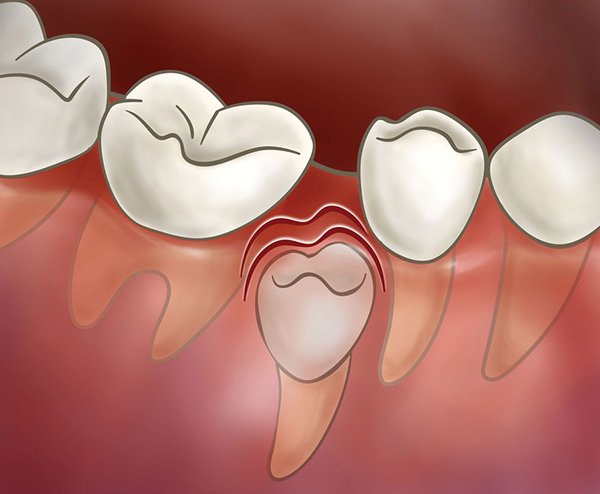

If baby teeth are lost too early due to decay or trauma and the space is left empty, adjacent teeth may tilt into the gap, leaving insufficient room for the permanent teeth to come in. This can lead to crowding and a greater need for orthodontic treatment later.

To prevent this, a space maintainer is used to preserve the space until the permanent tooth erupts in its proper position.